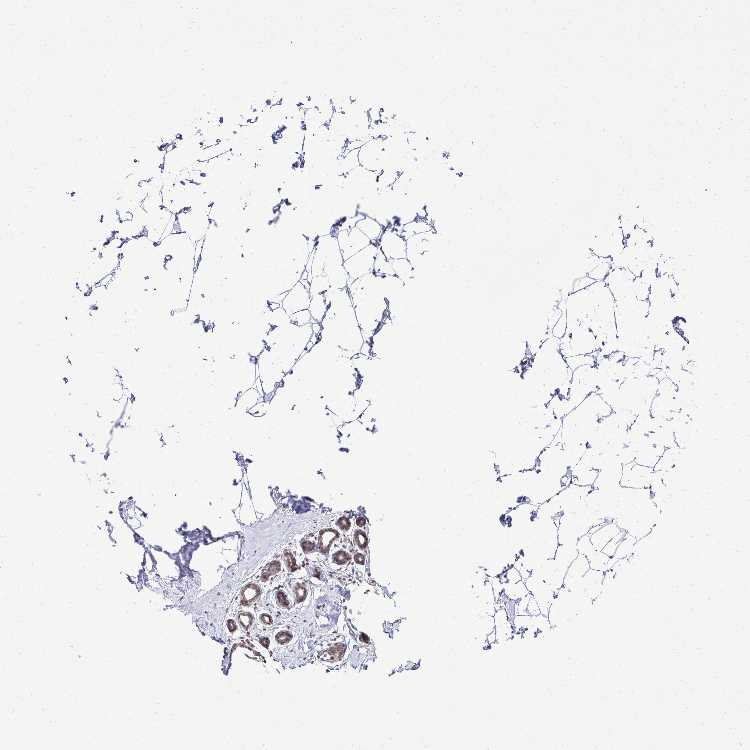

BREAST - Antibody stainingi

Antibody staining in the annotated cell types in the current human tissue is reported as not detected, low, medium, or high, based on conventional immunohistochemistry profiling in selected tissues. This score is based on the combination of the staining intensity and fraction of stained cells.

Each image is clickable and will lead to virtual microscopy that enables deeper exploration of all samples and also displays staining intensity scores, fraction scores and subcellular localization as well as patient and tissue information for each sample.

Antibody HPA039242Antibody CAB032896

Adipocytes Not detectedMedium

Glandular cells MediumMedium

Myoepithelial cells MediumMedium